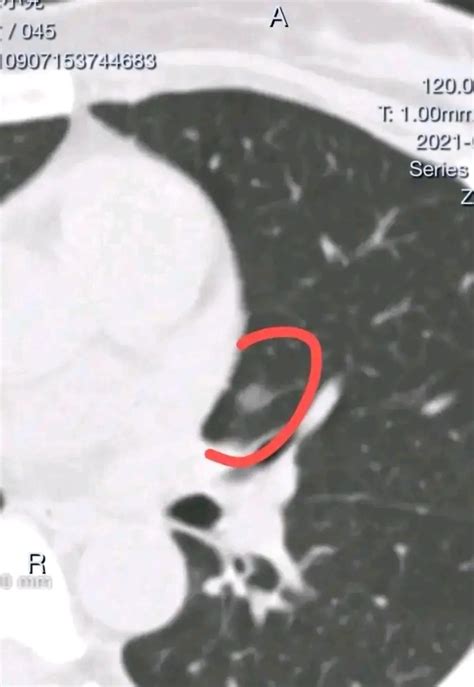

A ground glass nodule in lung imaging refers to a specific appearance on a high-resolution computed tomography (CT) scan. It looks like a hazy, foggy, or “ground-glass” opacity where the lung tissue appears slightly denser than normal but is not dense enough to completely obscure the underlying blood vessels or bronchial structures. Unlike solid nodules, which appear as bright white spots, these lesions are semi-transparent on diagnostic imagery.

Radiologists use this term to describe an area where the air spaces in the lungs are partially filled with fluid, inflammation, or fibrous tissue. Because they are often small and asymptomatic, they are frequently discovered incidentally during screenings for other conditions, such as chronic coughs, heart issues, or routine check-ups for heavy smokers.